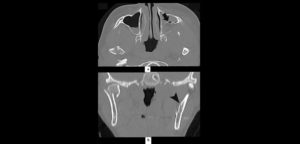

Durante las últimas décadas, el desarrollo de las técnicas no invasivas de imágenes ha permitido la visualización sin precedentes de las estructuras anatómicas de la